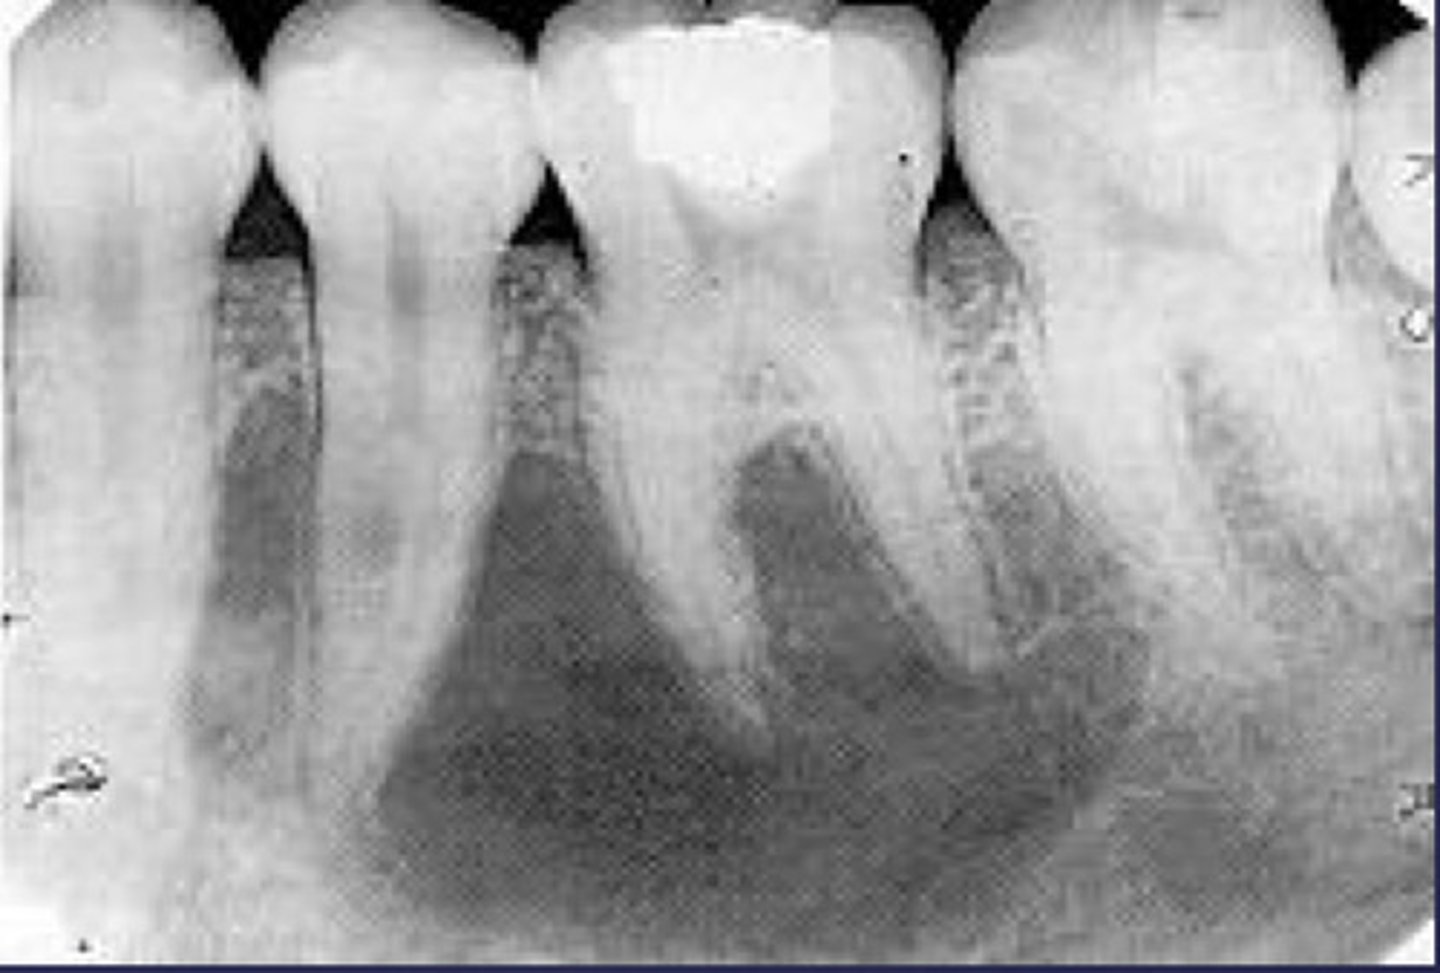

How would you describe the lesion?

- Periapical radiolucency associated with #30

- Has a band of sclerotic change extending from the apical radiolucency to the inferior alveolar canal and beyond

- Furcation involvement

(Furcation involvement as well as a band of sclerotic change extending from the apical radiolucency to the inferior alveolar canal and beyond)

What category would you put this lesion into?

Inflammation

what could be a differential diagnosis for this lesion? (select all that apply)

A. PCOD

B. multiple myeloma

C. apical rarefying osteitis

D. chronic sclerosing osteomyelitis

Also note apical rarefying osteitis #14 ( remnant root fragments, no crown due to caries)